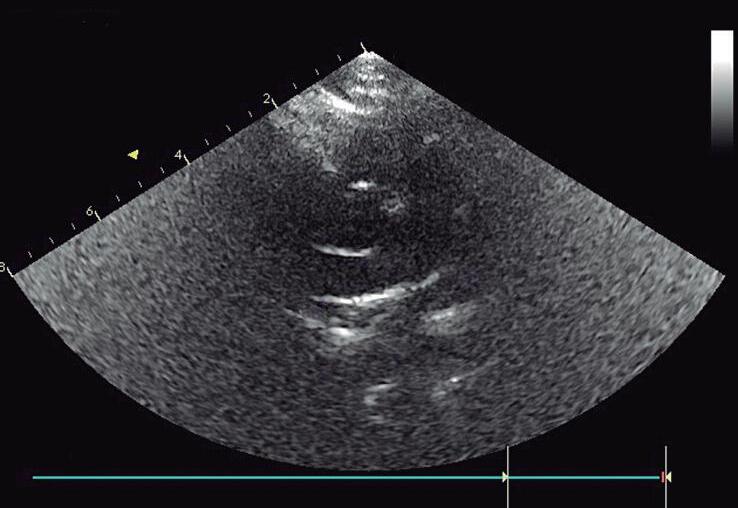

O plano subcostal eixo longo 4 câmaras e vias de saída do VE e do VD são obtidos com o transdutor na região subxifoide, inclinando-o da região caudal para a cranial do paciente (do ápice para a base do coração) (▶ Vídeo 1-10). O plano subcostal 4 câmaras demonstra os átrios e os ventrículos direito e esquerdo. É o plano preferencial para avaliar o septo interatrial, pois o feixe de ultrassom é perpendicular ao septo ( ▶ Vídeo 1-11). O pericárdio pode ser avaliado, assim como a função biventricular. Ainda nessa posição, com uma discreta movimentação posterior do transdutor, quando em posição habitual, o seio coronário é visto drenando para o átrio direito (AD), semelhante ao plano apical 4 câmaras. Com uma angulação mais cranial do transdutor (base do coração) é possível obter o VE com sua via de saída subvalvar, valvar e aorta ascendente (▶ Vídeo 1-12). Também podem ser avaliados nesse plano: o septo interventricular (membranoso, subaórtico e muscular trabecular) e a junção da veia cava superior com o AD. Numa angulação cranial mais distal, é possível obter o eixo longo do VD e avaliar o VD, o AD, a via de saída do VD (região subvalvar, valvar e o tronco da AP), possibilitando a avaliação de lesões obstrutivas

Veia cava inferior e superior

Veias hepáticas

Aorta abdominal

átrios direito e esquerdo

Septo interatrial

Septo interventricular

Seio coronário

Valvas mitral, tricúspide, aórtica e pulmonar

Veias pulmonares

Ventrículos esquerdo e direito

da via de saída do VD, como na tetralogia de Fallot, contratilidade do AD (análise qualitativa) e lesões da valva tricúspide.